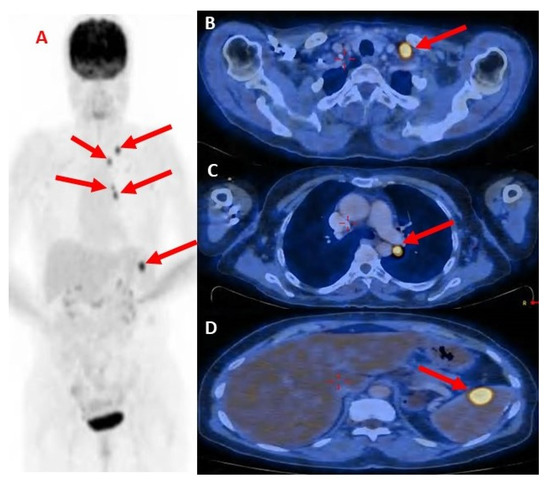

Positron emission tomography-computed tomography (PET-CT) showed hyper-metabolic uptake in the LUL mass (1.7 cm in diameter) and multiple metastases in the mediastinal lymph nodes and the hilum of the left lung. Hyper-metabolic uptake and enlargement of the lymph nodes in the left supraclavicular area (1.1 cm in diameter) and a hyper-metabolic uptake in the spleen (1.2 cm in diameter) were also seen (Figure 3). Magnetic resonance imaging (MRI) of the head showed no evidence of metastatic disease. The presumptive clinical diagnosis was stage T1 N3 M1 (stage 4) non-small cell lung cancer. Molecular testing showed programmed death ligand (PDL)-1 staining at 75%, positive for EGFR mutations (p.Glu746_Ser752delinsVal.), and was negative for ALK rearrangement and BRAF.

Figure 3.

(A) PET-CT scan showing the spread of metastatic disease; (B) showing hyper-metabolic uptake in the LUL mass; (C) Hypermetabolic uptake and enlargement of the lymph nodes in the left supraclavicular area; and (D) hyper-metabolic uptake in the spleen. Red arrows indicate metastasis.